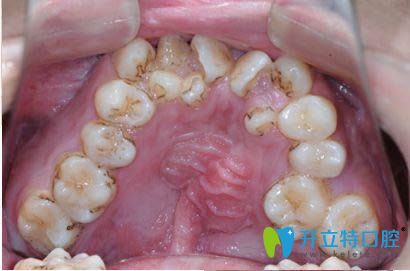

牙齒不齊容易引起牙周病及齲齒

張?jiān)洪L表示,首先,年齡大了以后,牙齒是否會早掉,主要取決于牙周情況的好壞(包括牙周膜、牙槽骨、牙齦),還有就是蛀牙齲齒的因素。整個(gè)牙齒被蛀空了容易掉,當(dāng)牙周長期炎癥侵蝕,導(dǎo)致骨頭吸收,就如水土流失一般,牙齒也容易掉。而引起牙周炎的往往是牙齒菌斑微生物和牙結(jié)石。